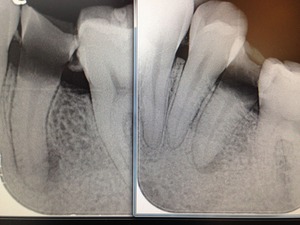

神経の管にはレントゲンや手術用顕微鏡でも見えない細いクダがたくさんあります。

歯科医が消毒できるのは、せいぜいレントゲンで見える本管、木の幹のような部分だけです。